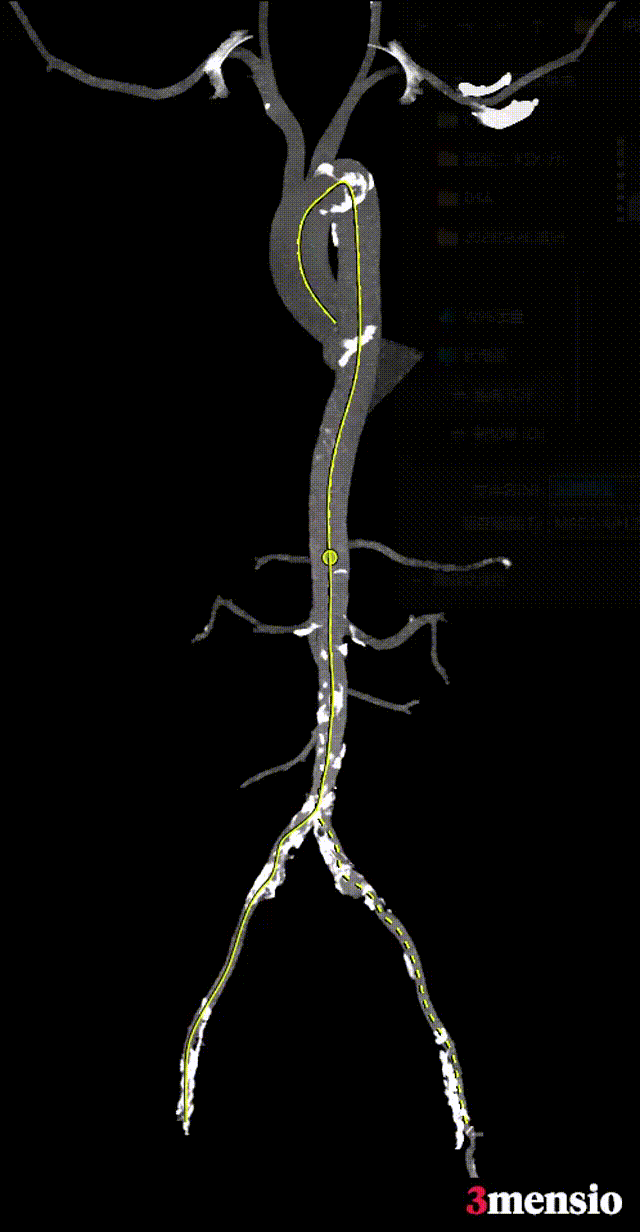

术前CT影像评估

根部概览

Annulus:Φ24.3mm

19.5mm*28.5mm

LVOT:Φ27.2mm

18.8mm*30.4mm

SOV-LCC:31.7mm

SOV-RCC:28.9mm

SOV-NCC:31.8mm

STJ:Φ27.0mm

26.0mm*27.9mm

AOO MAX:Φ30.9mm

29.5mm*31.6mm

钙化分布情况:

冠脉风险评估:

左右冠脉大量钙化分布,拟同期行冠脉搭桥。

左心室评估:

心室内径明显扩大,心室壁厚度可。

弓部及入路评估:

双侧股动脉严重钙化病变,内径小,挑战高(术中探查股动脉钙化严重,无穿刺进鞘部位)。

颈动脉入路偏细,术中易引发脑缺血等并发症。

右侧锁骨下动脉可作为备选入路。

经升主动脉入路需评估升主动脉长度及钙化病变情况。